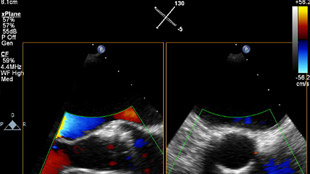

تم تشخيص أحد المرضى لديك بتضيّق في الصمام الأورطي المصحوب بأعراض. يبلغ عمر المريضة 85 عامًا وهي تعاني من السكري وارتفاع ضغط الدم. أنت تدرك خطورة وضعها الصحي ما يجعلها غير مناسبة لجراحة القلب ولكن يسمح لها بأن تكون مرشحة لاستبدال الصمام الأورطي باستخدام القسطرة (TAVR). في يومنا هذا، تمنح حلول التصوير المبتكرة والأجهزة التي تعمل عن طريق الجلد الأمل لبعض المرضى الذين لا تتوفر لهم حتى الآن أي خيارات علاجية أخرى.